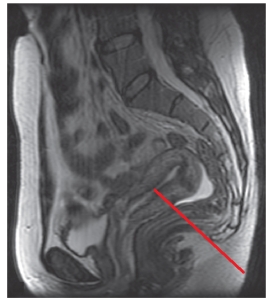

22

Identify the imaging plane,anatomy,and modality in this figure.

A) Midcoronal CT,female pelvis

B) Midcoronal CT,male pelvis

C) Midsagittal MRI,female pelvis

D) Midsagittal MRI,male pelvis

23

The line on this image labels the:

A) uterine cavity.

B) urinary bladder.

C) rectum.

D) kidney.